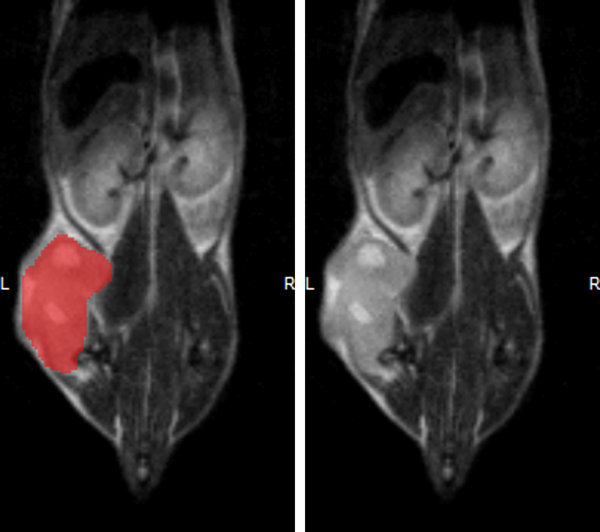

Hindlimb tumor growth: Monitoring the growth of xenograft tumor grown in the mouse hindlimb is identified with T2-weighted images. Segmentation of tumor region of interests (in red) on each tumor-containing slice allows accurate volume quantification. Image Credit: Scintica Instrumentation Inc

Monitoring the growth of xenograft tumor grown in the mouse hindlimb is identified with T2-weighted images. Segmentation of tumor region of interests (in red) on each tumor-containing slice allows accurate volume quantification. Image Credit: Scintica Instrumentation Inc